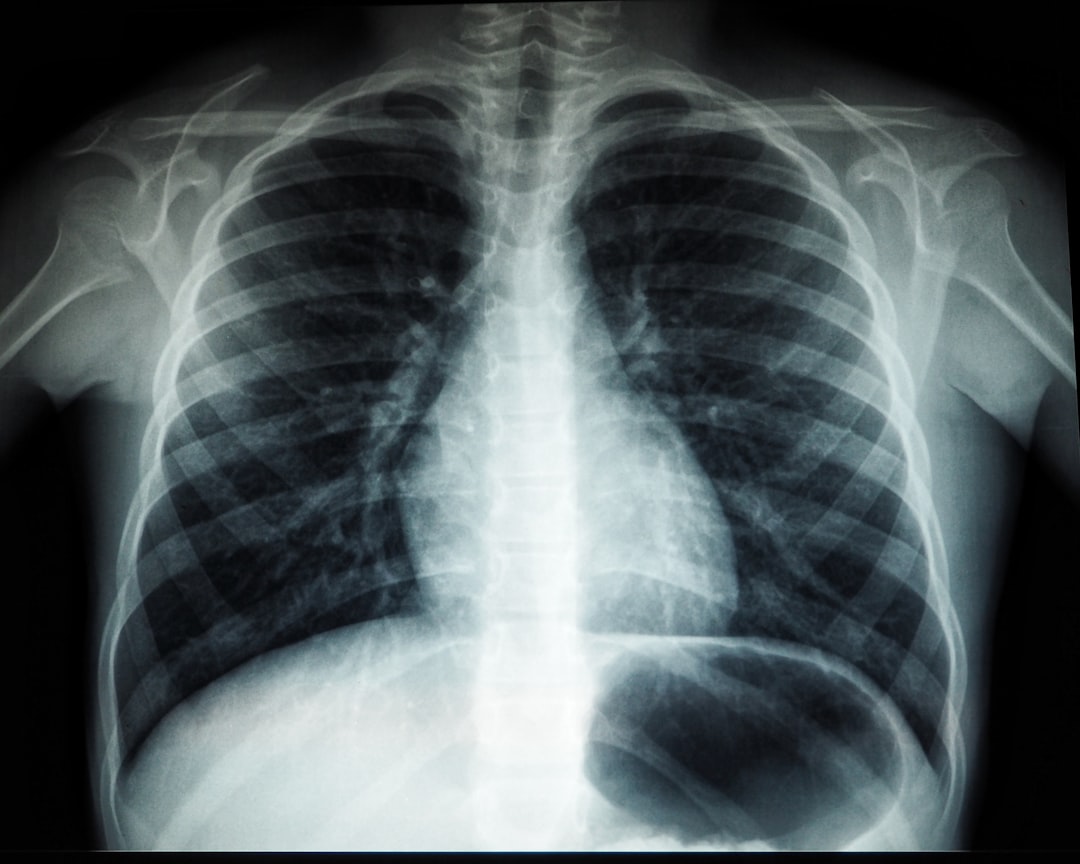

보건소 결핵검사란?

보건소 결핵검사는 결핵 예방을 위한 필수적인 검사입니다. 결핵은 전염성이 강한 질병으로, 조기 발견이 중요합니다. 한국의 보건소에서는 여러 종류의 결핵검사를 제공하며, 그 중 가장 흔한 것이 결핵균 감염 여부를 확인하기 위한 검사입니다. 보건소 결핵검사를 통해 많은 사람들이 결핵으로부터 안전할 수 있는 방법을 모색하고 있습니다. 이 검사는 비교적 간단하게 진행되며 최소한의 비용으로 이루어집니다. 검사 방법에 대한 더 깊은 이야기는 다음에서 다뤄보겠습니다. 그래서 여러분의 궁금증을 해소하기 위해 계속 읽어보세요!

검사 방법

보건소 결핵검사 방법에는 여러 가지가 있습니다. 가장 일반적인 방법은 튜베르쿨린 피부 검사와 혈액 검사입니다. 피부 검사는 팔에 작은 주사를 통해 이루어지며, 이후 48시간 후에 결과를 확인합니다. 혈액 검사는 검사 결과를 신속하게 받아볼 수 있는 장점이 있습니다. 개인적으로 이 검사들은 매우 간편하고 부담이 적었습니다! 여러분도 이렇게 간단하게 진행될 수 있다는 사실에 안도감을 느낄 것입니다.